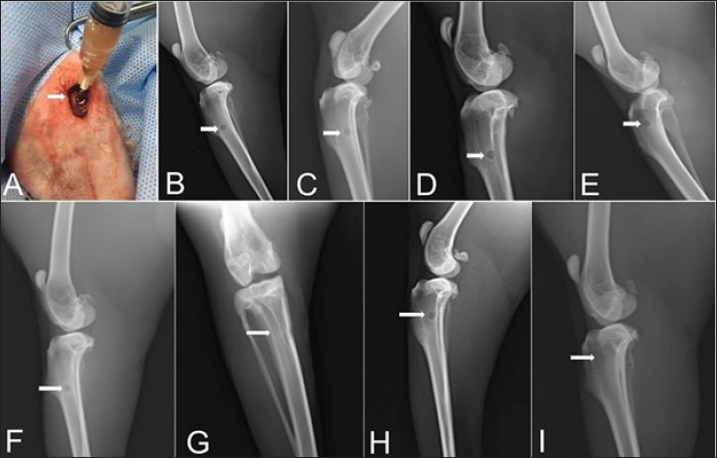

Zero-time radiographic evaluation following surgery demonstrated radiolucency; bone defect at the proximal part of the tibial tuberosity in all studied groups (Fig. 5). Whereas, postoperative follow-up radiographs (≤ 2 months) of the studied rabbits revealed a significant difference (p < 0.05) in bone regeneration between rabbits treated with Ag-NPs FG gel (group 2) at the fourth week and onward in comparison to the control group, and at the eighth week in comparison to rabbits treated with plain gel (group 3), and rabbits treated with FG gel (group 4) as depicted in (Fig. 5) and (Table 1).

Fig. 4. A) Viscosity profile of FG and AgNPs-FG loaded hydrogels at different shear rates; B) Rheograms of FG and AgNPs-FG loaded hydrogels at different shear stress values.Fig. 5. Skin incision at the medial aspect of the proximal end of the right tibia with the injection of AgNPs-FG-gel at the bone defect (A), immediate postoperative lateral radiographs of bone defect at tibia + normal saline control group (group1) (B), bone defect at tibia + AgNPs-FG (group 2) (C), bone defect at tibia + plain gel (group 3) (D), and bone defect at tibia + FG-gel (group 4) (E). Postoperative (day 56) lateral radiographs of bone defect at tibia + normal saline, (group1) (F), Cranio-caudal radiograph of bone defect at tibia + AgNPs-FG (group 2) (G), bone defect at tibia + plain gel (group 3) (H), and bone defect at tibia + FG-gel (group 4) (I). Please note complete healing in (G) compared to other studied groups.

Although the radiographic examination is the standard tool for the assessment and follow up of the healing process of various fractures, however, great efforts have been made in previous research toward developing new techniques for following the progress of bone fracture healing. Therefore, the collaboration between the radiographic, BTMs, and histopathological findings used in this study provides a promising tool for the subjective assessment of fracture repair. These results were inconsistent with El Shafaey et al. (2014), and Al-Sobayil et al. (2020). Postoperative radiographic follow-up (≤ 2 months) of the operated rabbits revealed a significant difference (p < 0.05) in bone regeneration between rabbits treated with Ag-NPs-FG gel (group 2) at the fourth week and onward compared to the control group and at the eighth week in comparison to rabbits treated with plain gel (group 3), and rabbits treated with FG-gel (group 4).